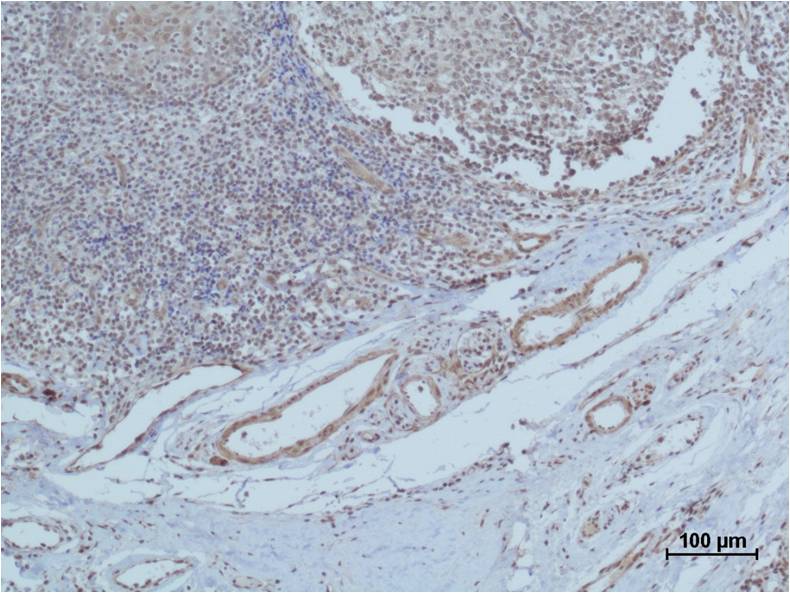

Product name: HIF-1β/ARNT Rabbit pAb

Dilutions: WB 1:1,000-2,000?? IHC 1:200-500

Background: Hypoxia-inducible factors (HIFs) are transcription factors that respond to changes in available oxygen in the cellular environment, to be specific, to decreases in oxygen, or hypoxia.This protein is required for the ligand-binding subunit to translocate from the cytosol to the nucleus after ligand binding.